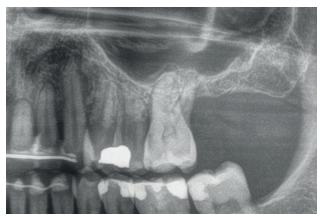

En todos los casos, se realizó un diagnóstico basado en modelos de estudio, exploración intraoral del paciente y realización de un Cone-beam analizado mediante el software específico BTI-Scan III (Biotechnology Institute, Vitoria, Alava, España).

Fueron reclutados diez pacientes que cumplieron los criterios de inclusión, en los que fueron insertados 20 implantes. Tres de ellos fueron mujeres y la edad media fue de 72 (+/- 6 años). Ninguno de los pacientes era fumador en el momento de la cirugía y no presentaban enfermedad periodontal activa. El diámetro mayoritario de los implantes incluidos en el estudio fue de 5 mm (60%), seguido de 4,5, 5,5 y 4,75 mm (13,33% cada uno de ellos). La longitud predominante fue la de 5,5 mm (86,6% de los casos), siendo el 13,4% restante implantes de 4,5 mm de longitud. Las posiciones más habituales fueron para los segundos molares (molares 27 y 17) representando un 55% de los casos.

En las Figuras 2- 19 se muestra uno de los casos incluidos en el estudio.